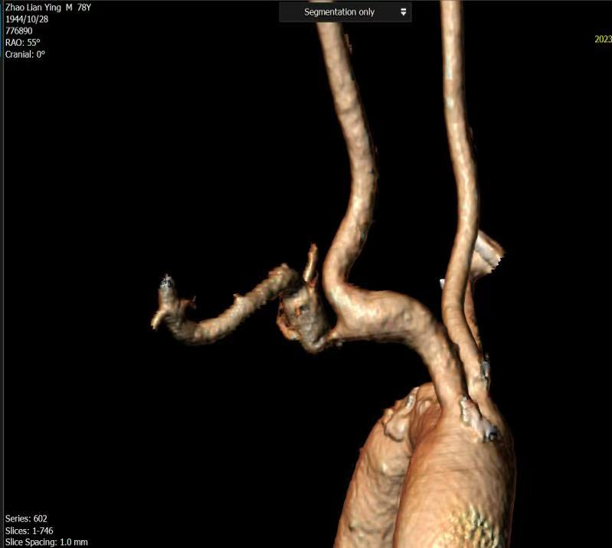

常规病变的精准支架释放:

即使是常规狭窄病变,采用CTA预定的角度(如 RAO 50° CRA 0°)也能实现支架的精准释放,确保完全覆盖病变且不影响重要分支。

图:CTA确定投射角度

图:支架精准释放